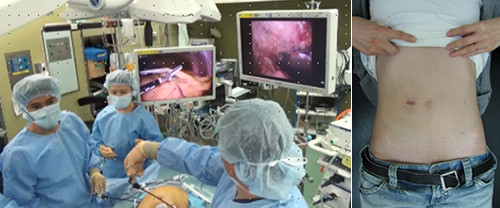

●各臓器の専門家が、腹腔鏡や胸腔鏡、手術支援ロボットを用いた低侵襲治療から多臓器合併切除などの拡大手術まで取り組みます。

高度な技術を要し、行っている施設の限られる肝胆膵疾患に対する腹腔鏡手術を手掛けています。日本内視鏡外科学会技術認定医そして肝臓内視鏡外科研究会理事、膵臓内視鏡外科研究会世話人である担当の板野医師は、腹腔鏡下の肝胆膵手術では、日本有数の症例経験数を誇っています。

きずが小さい手術(低侵襲手術:胸腔鏡・腹腔鏡手術[ロボット支援下手術を含む])を積極的に実施しています。進行がんに対しても安全性が確保できると判断した症例では実施しています。きずが小さいと美容面で有利なだけでなく、早期の回復が期待できます。

大腸癌を中心に潰瘍性大腸炎やクローン病などの外科的治療を要する疾患を対象に、原則すべての症例に対して腹腔鏡手術を行っております。

また、直腸癌に対しては、術前化学放射線療法を組み合わせることで、治療成績の向上や肛門温存に努めており、2018年4月に保険収載されたロボット支援手術も積極的に取り入れ、常に最新かつ最良の医療を提供することを目標としております。